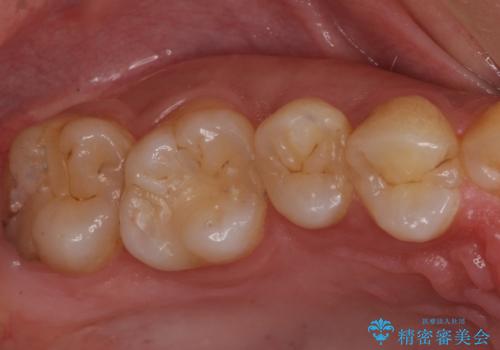

- 歯の健診にて来院。

レントゲンを撮った時にう蝕があったため、拡大鏡下でう蝕が残っていないか確認し

セラミックの詰め物(e-maxインレー)にて治療を行いました。